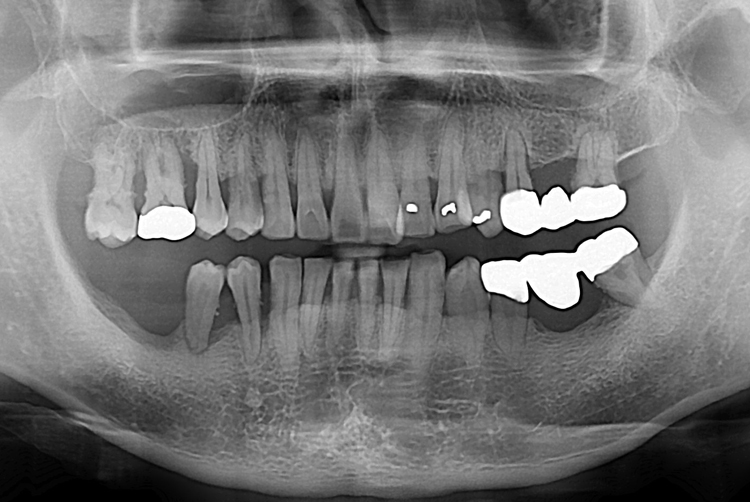

[임플란트] 어금니 임플란트

치료전 : 2017-06-13